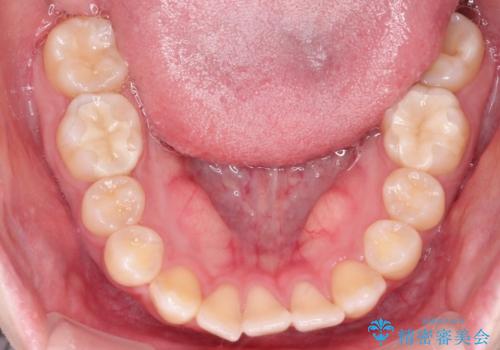

【インビザライン】歯を抜かずにできるだけ前歯を下げたい

- 前歯の前突を主訴に来院されました。

インビザライン を用いて、歯並びの改善を行うことができました。